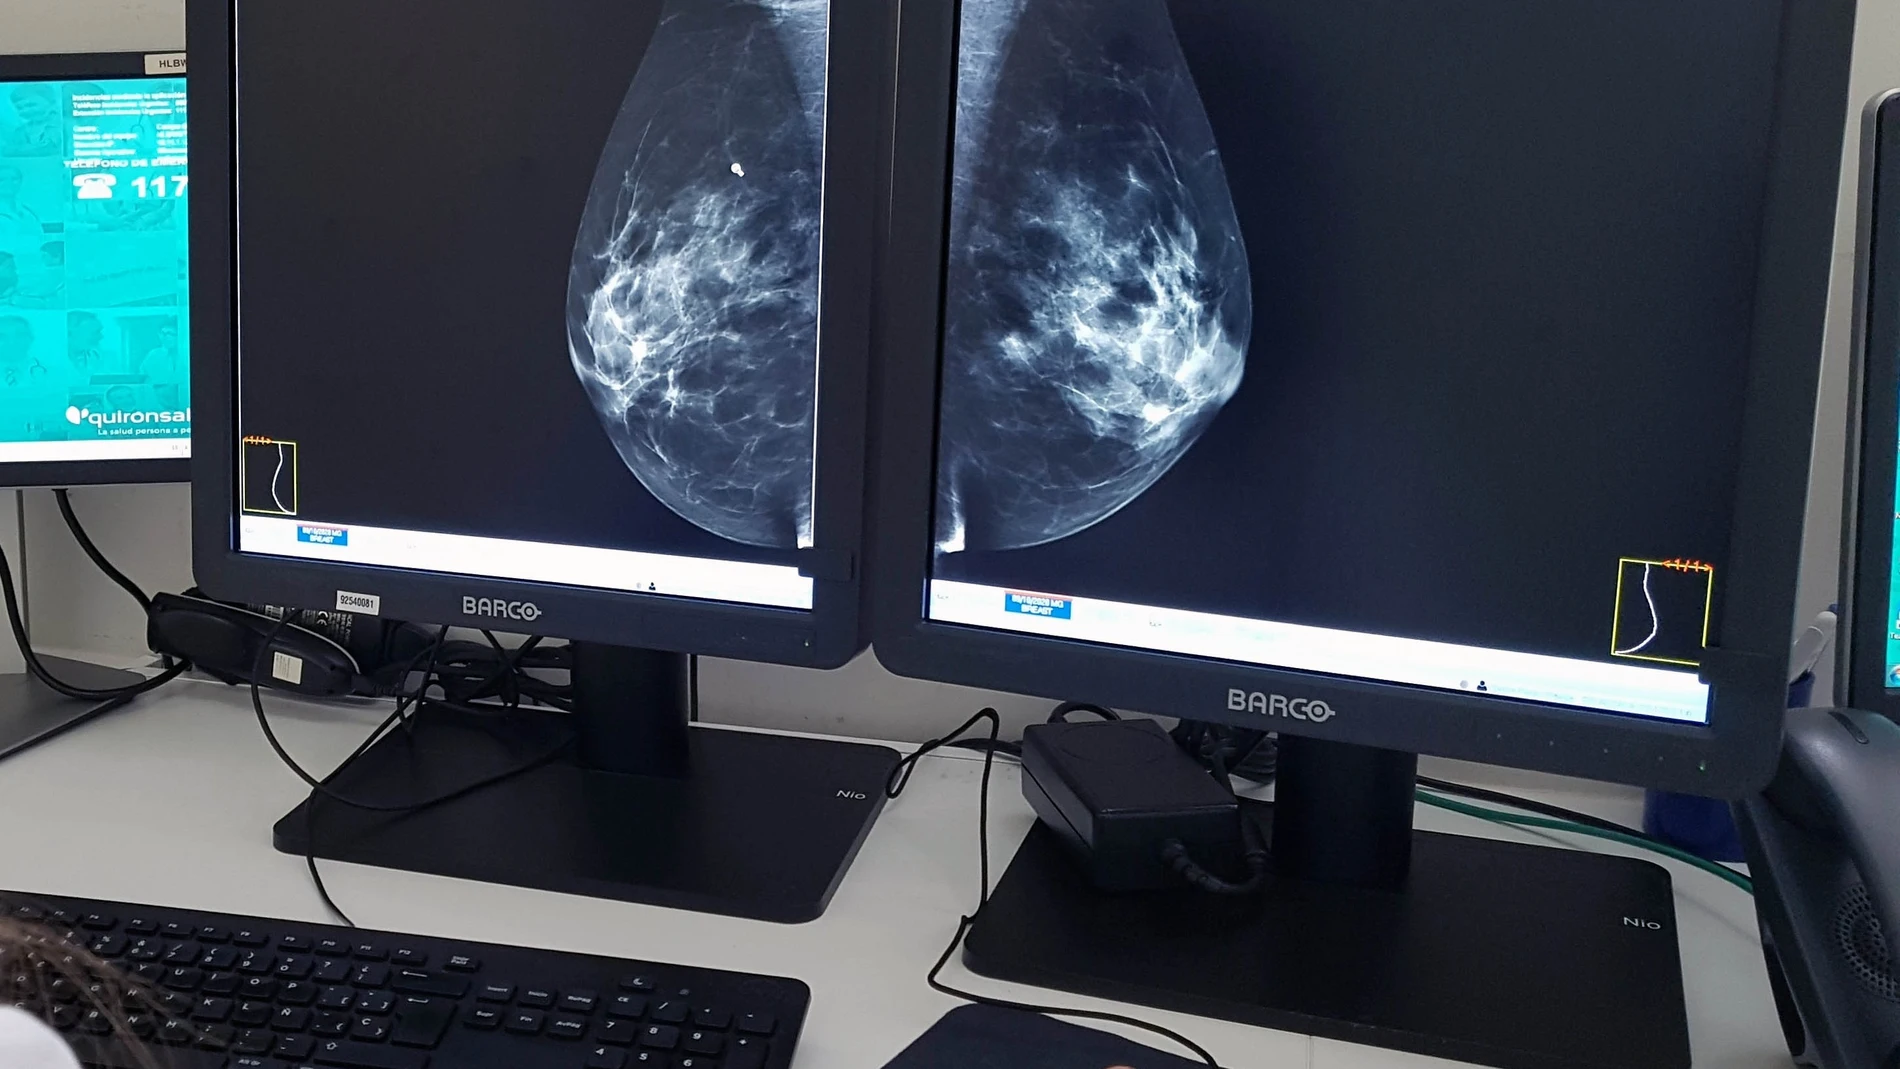

Un equipo de investigadores del Centro Médico de la Universidad de Georgetown halla un pequeño número de células en tumores que a menudo pasa desapercibido cuando se realizan biopsias para decidir una opción terapéutica

Sólo una pequeña cantidad de células que se encuentran en los tumores puede habilitar y “reclutar” otros tipos de células cercanas para hacer que el cáncer se disemine a otras partes del cuerpo, informan los científicos del Centro Oncológico Integral Georgetown Lombardi . Los investigadores han encontrado que las “células habilitadoras” comprenden alrededor del 20% o menos de las células en un tumor agresivo; su pequeño número puede explicar por qué a menudo se pasan por alto cuando se utilizan análisis de tejidos a granel para informar decisiones terapéuticas.

“La detección de estas células habilitadoras en cánceres de mama en etapa temprana podría predecir qué tumores son más agresivos y están destinados a hacer metástasis”, propone Ghada M. Sharif, de la Georgetown Lombardi y primera autora de este hallazgo. “La orientación terapéutica de las vulnerabilidades descubiertas en las células habilitadoras, como las variantes de empalme, podría representar un nuevo enfoque para prevenir la progresión maligna del cáncer de mama”, añade.

Este hallazgo es particularmente relevante en los cánceres de mama triple negativos que pueden ser agresivos y difíciles de tratar. Estos tipos de cáncer generalmente comienzan como tumores no malignos, llamados carcinoma ductal in situ (DCIS), pero entre el 5 y el 10% de los casos puede progresar rápidamente a tumores malignos. Los investigadores encontraron que AIB1-Delta4 se encuentra en niveles elevados en mujeres con DCIS de mayor riesgo.

El próximo paso de los investigadores será realizar varios análisis de células individuales en muestras de tejido humano. “Estamos en un punto de inflexión en la forma en que analizamos las muestras de tumores”, explica Riegel. “Hace sólo unos años era impensable y poco práctico observar cada célula en una muestra de tejido. Pero la tecnología avanza, y creemos que en los próximos años observar cada célula nos permitirá determinar qué células, incluso si son pequeños en número, realmente están impulsando la progresión del cáncer “, asegura.